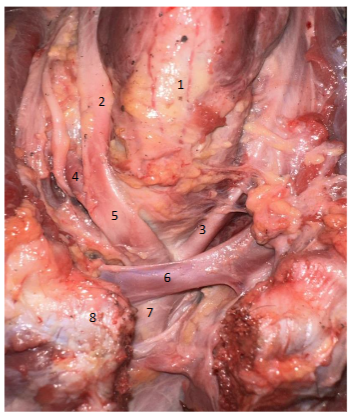

1. Trachea 2. Right common carotid 3. Left common carotid 4. Right subclavian artery 5. Brachiocephalic artery 6. Left brachiocephalic vein 7. Aorta 8. Sternum